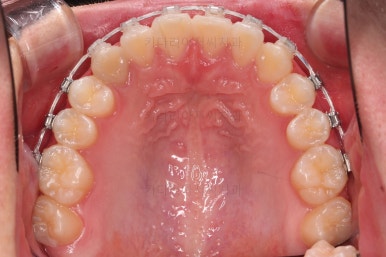

틈이 다 모였고 교합도 많이 좋아졌죠?

끝내도 될까요?

안됩니다.

간혹 교정장치를 풀자마자 유지장치를 했음에도 틈새가 다시 벌어지는 경우가 많은데요.

일부러 힘을 뺐다가 느슨하게 해보았다가 틈새가 다시 안벌어지는지를 충분히 확인한 후 치료를 종료하게 됩니다.

그래서 적극적인 치료는 진작에 끝났다 하더라도 치료 말미에 기다리는 시간이 많이 소요되는 치료가 이번 치료입니다.

안정성을 충분히 확인한 뒤 치료를 종료합니다.

전후 사진을 비교해 볼게요.

악궁확장을 통해 위아래 악궁의 크기 조화를 맞췄고, 틈새도 모았으며 교합도 적절히 마무리를 했습니다.

웃는 모습도 훨씬 예뻐졌네요.

향후 유지관리가 다른 분들보다 훨씬 중요한 상황이라 볼 수 있겠습니다.